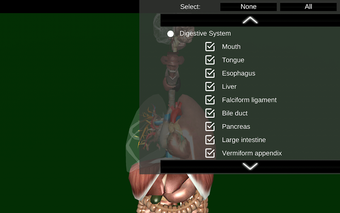

您可以触摸每个器官,如心脏、大脑、肺、生殖系统、肝脏、肠道、卵巢、睾丸、胃、肾脏等。

它对所有人都有用,甚至对学生也有用,因为每个解剖器官都以不同的颜色显示。